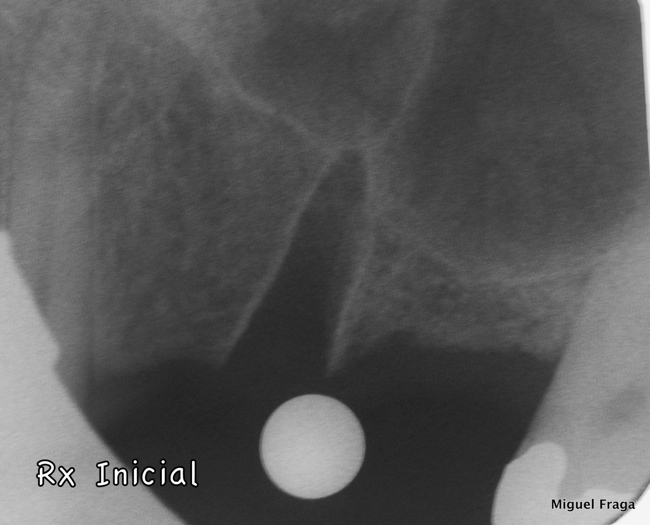

Paciente, com ausência dentes 24 e 26, e com 25 indicado para extração. Colocaram-se implantes no local do 24 e 26. Neste último, a altura óssea era de 3 mm, e por isso o protocolo, consistiu na preparação com broca aquém da cortical do seio maxilar. Seguidamente utilizaram-se osteótomos, com os quais provocamos a fractura da cortical e a elevamos. A membrana de Schneider foi elevada e o seio maxilar foi preenchido através do leito implantar. Para executar este tipo de procedimentos utilizamos Osteotomos e “magnetic mallet”. No essencial esta técnica é baseada no protocolo de Summers, e, entre outros, no livro “The Percrestal Sinuslift” de Georg Watzek.

Neste caso com reduzida altura óssea foi possível num mesmo tempo cirúrgico colocar implantes, elevar o seio e ser minimamente invasivo. Ao fim 5 meses o caso estava reabilitado proteticamente.